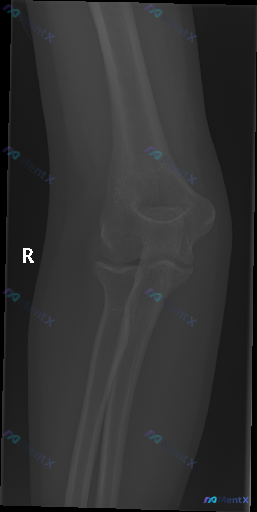

这张右侧肘侧位X光报了“未见明确骨折”,但前提说“存在异常”,第一反应会找什么?

前提:用户明确说“这张图像存在异常”,然后给出了一张右侧肘关节侧位X光片的分析。

先放影像报告里的“阴性描述”:

- 骨皮质连续,肱骨远端、桡骨头颈、尺骨鹰嘴冠突都没见明确断裂线

- 前脂肪垫征正常,后脂肪垫征阴性,关节腔好像没有明显积血积液

- 肱桡、肱尺关节对位正常,间隙不宽不窄

- 软组织没见明显肿胀,没有游离骨块或异物

- 骨质密度还行,没明显退变增生

但综合“存在异常”的前提,分析里提了几个方向——不过先不说,想听听大家的思路:

- 第一眼看到这种“影像报没事但前提说有异常”的肘外伤侧位片,会优先往哪里想?

- 如果是你在急诊,接下来第一步会做什么?